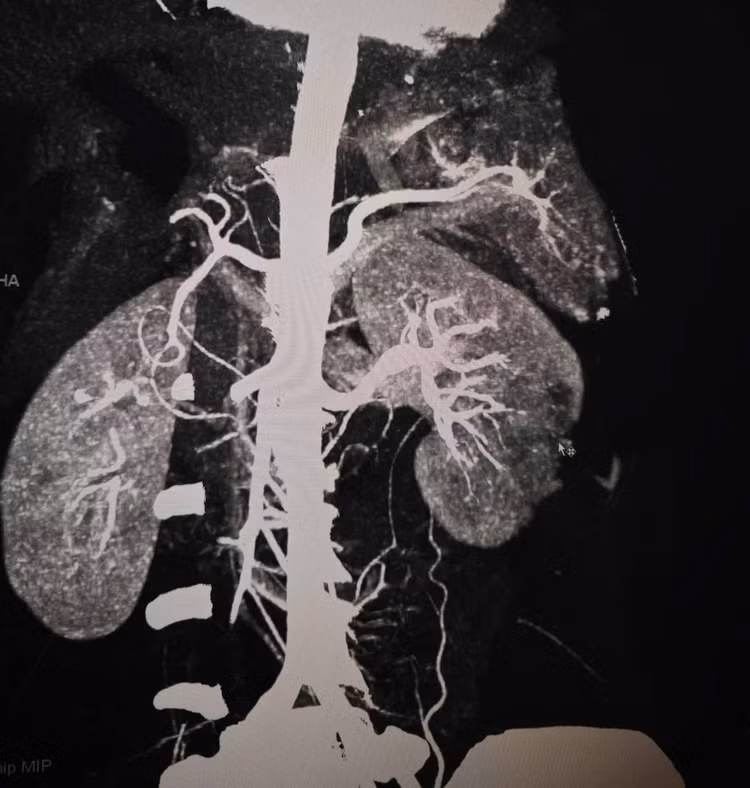

Hình ảnh thận vỡ trên phim chụp - Ảnh BVCC

Kết quả chụp CT cho thấy tổn thương rất nặng: vỡ lách phức tạp, vỡ thận độ IV có giả phình mạch và chảy máu hoạt động, kèm tràn máu ổ bụng. Tình trạng này có thể gây sốc mất máu bất cứ lúc nào nếu không xử trí khẩn cấp.